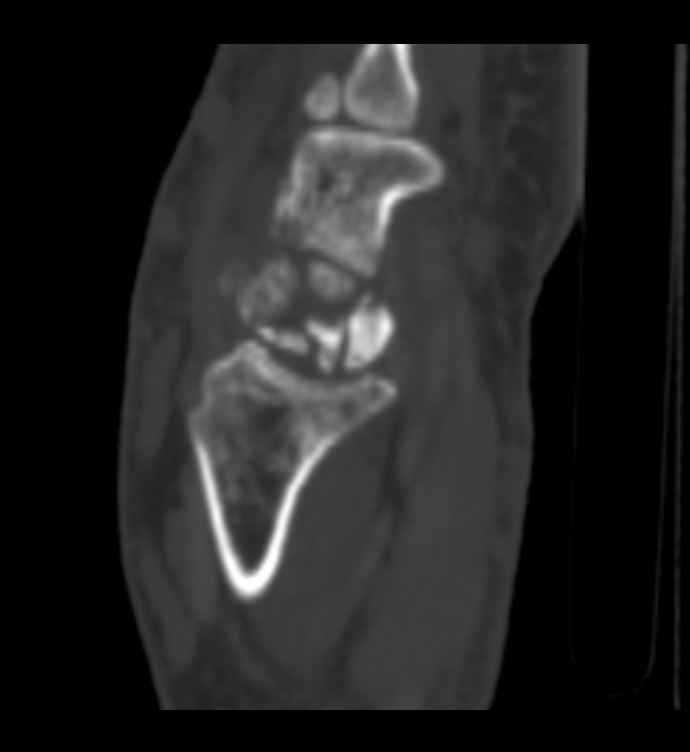

После 6-го коммента добавляю КТ. DICOM тут: http://files.mail.ru/A64E4C объём 14,5 МВ.

К большому моему сожалению, методом КТ не владею. Попробую описать то, что вижу, в надежде, что Вы поправите. Множественные полиоссальные очаги костной деструкции с достаточно четкими контурами (склеротический ободок?), местами с нарушением целостности кортикального слоя. В головчатой кости в деструктивном очаге плотная тень, похожая на секвестр. Полулунная фрагментирована соответственно ас/некрозу. Суставные щели сохранены, хотя соотношения костей запястья в горизонтальной плоскости выглядят не нормально. Мягкие ткани увеличены в обЪеме, дифференцировка структур по ладонной поверхности сохранена, по тыльной поверхности ближе к локтефой четкость теряется, на этом фоне непонятные мне включения. + отмечается расширение сосудистых теней. Остеомиелит и флегмона остаются у меня под большим сомнением. И характерных для нейротрофических нарушений напластований тоже не вижу (возможно, еще не срок?). При РА таких деструктивных изменений не встречала, и остеопороз под ?. Хотелось бы узнать Ваш вариант, уважаемая ЛГ.

Интраоссальные "секвестры" в запятье, а их два, это интраоссальные тофусы. Глыбчатые аморфные образования по плотности больше хряща, но меньше обызвествления, - это тофусы в мягких тканях. Кистовидные изменения костей запястья, с истончением коркового слоя и его частичным прерыванием - характерно для подагры.

Данных за гнойные затёки, абсцессы - нет. Есть инфильтрация клетчатки, объёмное увеличение мягких тканей, признаки синовита (тут МРТ б помогло лучше в плане визуализации).

Фрагментация и выраженное уплотнение полулунной кости - исход болезни Кинбека, с удивительно слабо выраженными признаками ДОА. Пациент не помнит, чтоб в детстве-юности были проблемы с правой кистью... но кто знает, может, у него память избирательная)).

Дословно не помню, примерно так: по рентгенограммам написала в заключении фрагментацию и асептический некроз полулунной кости, кистовидные просветления головчатой и трехгранной кости (деструктивные?). По КТ в заключении: признаки последствия болезни Кинбека, подагрические тофусы мягких тканей, подагрические изменения костей запястья.